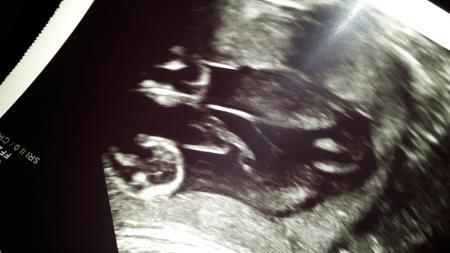

Hallo ihr lieben. .. Ich habe beim letzten Ultraschall erfahren dass unser Baby ein Mädchen werden soll ❤❤ Die schamlippen wirken sehr groß. Erkennt ihr auch dass es ein Mädel wird ? Danke

Bild zu Mädchen Outing? ?? - Schwanger - wer noch? Rund um die Schwangerschaft

Ja, eine Prinzessin ein junge würde da anders aussehen.

Eindeutig girly

100% Mädchen